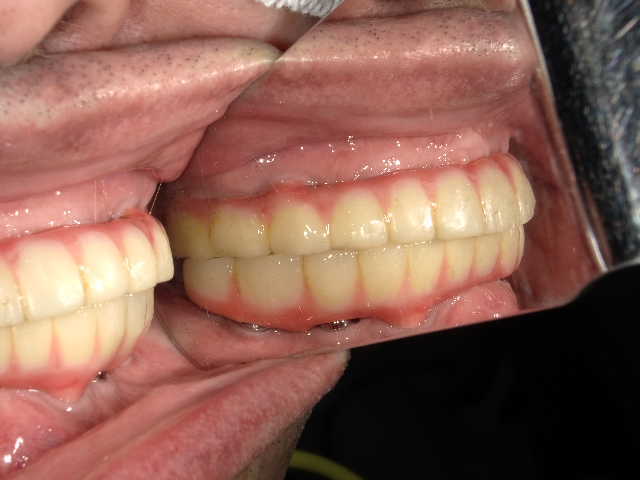

冨田先生についてCASE01 All on 4

下の歯は4本、上の歯は5本インプラントを埋め込み、上下ともに1日で歯をセットしました。上の歯に関しては、単に5本埋入すればいいという問題ではありません。

見た目が気になって笑えない。噛めない。

上の歯、下の歯のすべて

仮歯は1日、 治療期間3ヵ月

2,000,000~3,000,000円

- コメント

下の歯は4本、上の歯は5本インプラントを埋め込み、上下ともに1日で歯をセットしました。上の歯に関しては、単に5本埋入すればいいという問題ではありません。鼻の下の硬い骨を使ったり、ガミースマイル(=歯茎が見えてしまう笑顔)改善のために骨を削ったりする必要があります。また、下の歯は神経麻痺を回避するためにオトガイ孔(下の神経の出口)にプローブ(=先端の細い専用の器具)を挿入したりと細かなケアが大切です。

また、歯の治療をしてもどうしても歯を残すことが難しい状態に対しても、インプラントを埋めこむと同時に抜歯をすることで、All on 4の治療が可能になります。手術をしたその日のうちに仮歯が入るため、すぐに固定式の歯が必要だというような人にも向いている治療法です。

- 治療後のリスク

インプラント周囲炎、メンテナンスが必要

女性 58歳